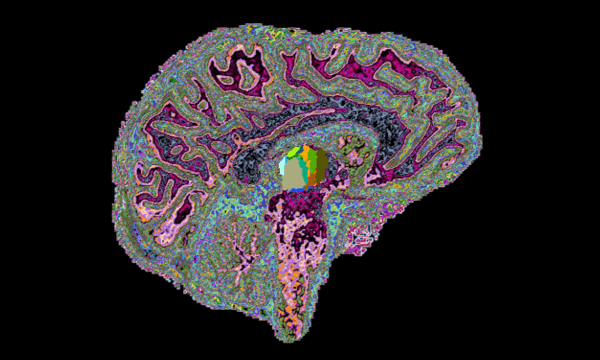

The Multiple Sclerosis (MS) Imaging Lab, directed by Eric Klawiter, MD, MSc, focuses on MS clinical research as well as the application and development of new imaging methods to better understand, diagnose and treat MS.

Through the use of novel imaging techniques, we examine changes in structural and functional brain networks in MS in relation to clinical outcomes such as cognition. The overall goal is to integrate novel imaging techniques into therapeutic clinical trials, which our lab is also involved with.

Our current imaging dataset consists of data from the 3T Connectom scanner and an ultra-high field 7T scanner on patients with MS including:

- Diffusion tensor imaging (DTI)

- Advanced diffusion imaging (i.e. Q-ball and axon diameter modeling)

Multi-modal Neuroimaging

The MS Imaging Laboratory is involved in various neuroimaging studies that implement established and novel techniques to examine structural and functional connectivity in relationship to cognitive dysfunction in MS.